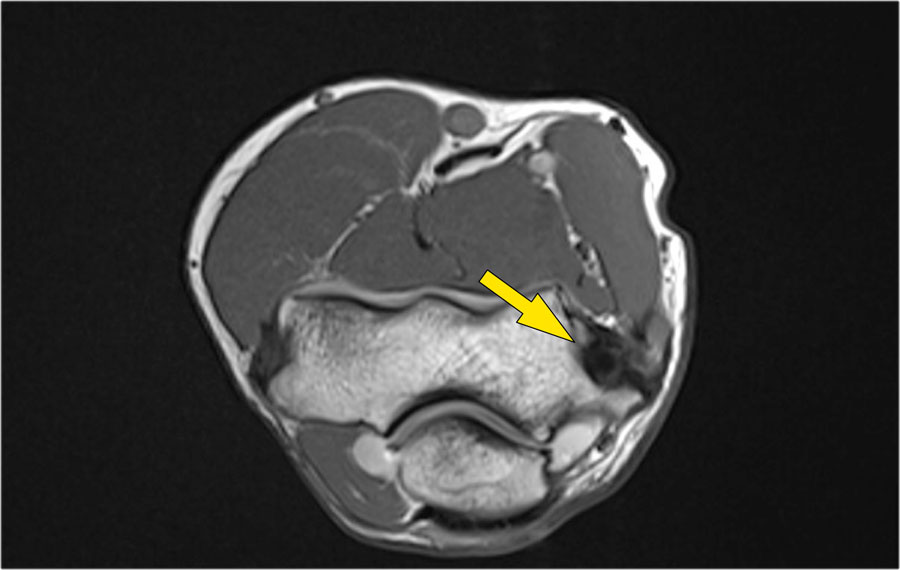

Những hình ảnh này của một nam giới 23 tuổi bị ngã chống tay khi đang trượt ván hai tuần trước.

Khi khám lâm sàng, ghi nhận giảm biên độ vận động khớp khuỷu và đau khi ấn dọc theo mặt ngoài.

Cấu trúc nào nằm phía sau chỏm quay trên hình ảnh cắt ngang?

Cấu trúc phía sau chỏm quay là dây chằng vòng.

Nó không đều và dày lên do hậu quả của trật khớp ra sau.